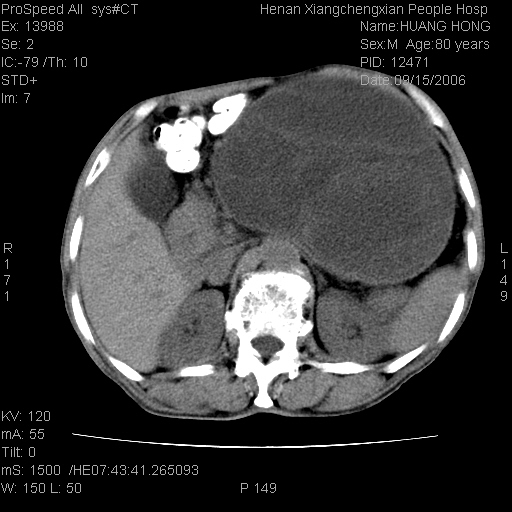

患者, 男, 80岁, 发现上腹部包块1年余,无其它不适.2006-9-14ct片是喝水后扫描2006-9-15ct片没喝水扫描![]() ![]() ![]() ![]() ![]() ![]() ![]() ![]() ![]() ![]() ![]() ![]() ![]() ![]() ![]() ![]() 以上是喝水片 以下是空腹片 ![]() ![]() ![]() ![]() ![]() ![]() ![]() ![]() ![]() ![]() ![]() ![]() ct:胰腺前方、肝脏与胃之间可见巨大类圆形囊性低密度影,大小约152mmx145mmx118mm,上缘平t11椎体上缘,下缘平l3椎体下缘,密度均匀,ct值15hu,其内呈多房分隔,囊壁薄且光滑,边界清晰,周围组织及器官明显受压。肝脏实质内未见异常密度影,胆囊未见异常,胰腺密度未见异常,脾脏大小、形态及密度未见异常,腹膜后间隙未见肿大淋巴结影。 印象:胰腺前方、肝脏与胃之间巨大类圆形囊性低密度影.性质待定。多考虑:.肠系膜巨大囊肿。 守望可可西里发言:支持楼主,考虑肠系膜囊肿,多为小肠系膜。 ysxyy发言:我总觉得这个病人虽然很像肠系膜囊肿,但还是应该强化一下; 下面这几幅图里肿块和主动脉的关系不太清,不知能否除外血管性来源? ![]() ![]() ![]() 病理结果:横结肠系膜间叶瘤.部分区域间质细胞增生活跃. 病理图片 ![]() 良性间叶瘤:是指由两种或两种以上的间叶组织所构成的混合性肿瘤.肿瘤仅发生在腹膜后和肠系膜,.前者较后者多发.良性间叶瘤常发生在肾或四肢,腹膜后较少见,各年龄均可发病.女多与男,预后较好,但术后易复法. 恶性间叶瘤:由两种以上恶性间叶组织成分组成. 光镜:肿瘤由脂肪/血管/平滑肌构成. 原贴地址: http://www.radinet.com.cn/forum_view.asp?forum_id=4&view_id=16217 ok |